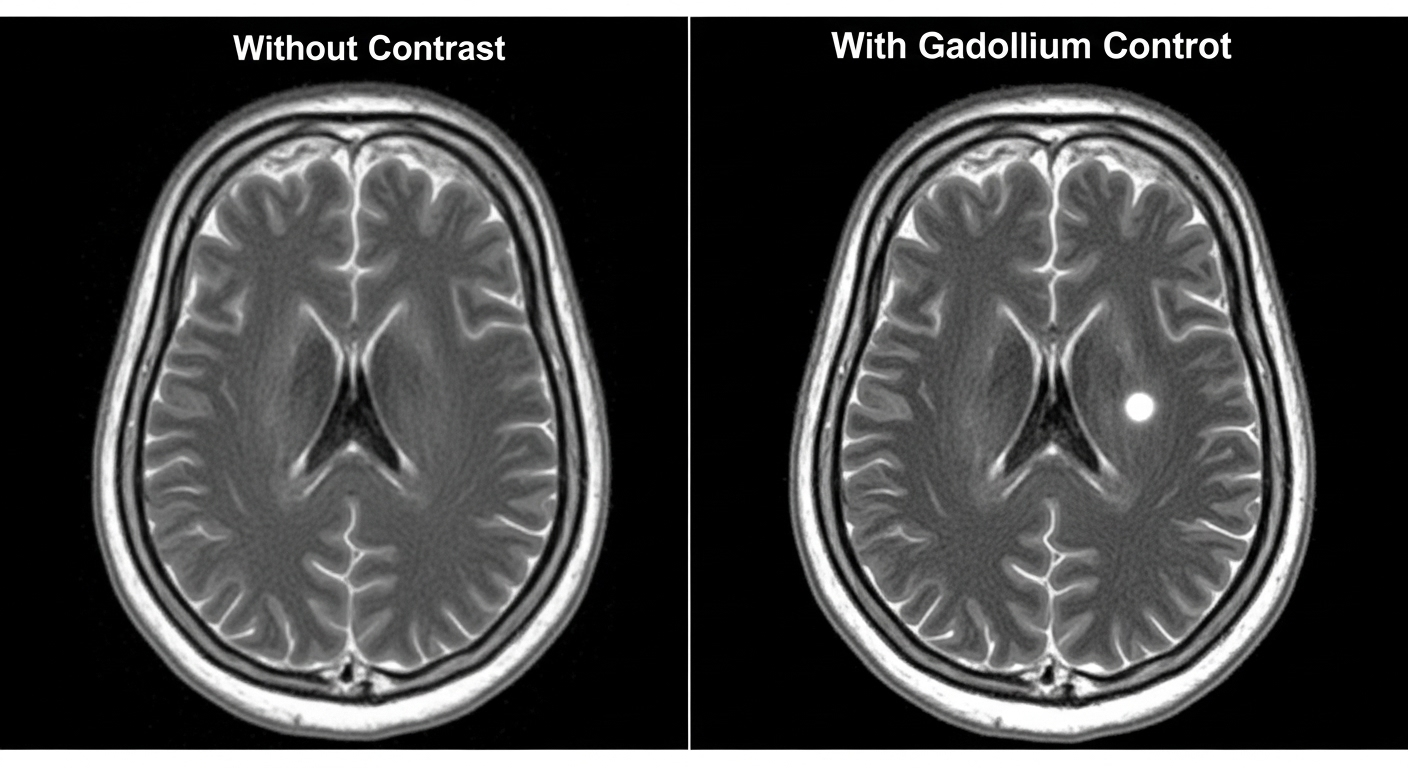

Le gadolinium, c’est un métal que l’on trouve naturellement dans la croûte terrestre. En médecine, on l’utilise pour les IRM parce qu’il aide à ‘surligner’ certaines parties de notre corps, ce qui rend les images beaucoup plus nettes et détaillées. Normalement, une fois l’examen terminé, il est censé être éliminé de notre corps par les urines. Mais attention, toutes les IRM ne nécessitent pas ce produit. On l’utilise surtout pour des examens du cerveau, des seins ou de l’abdomen. Pour des IRM de la colonne vertébrale ou des articulations, ce n’est généralement pas nécessaire.